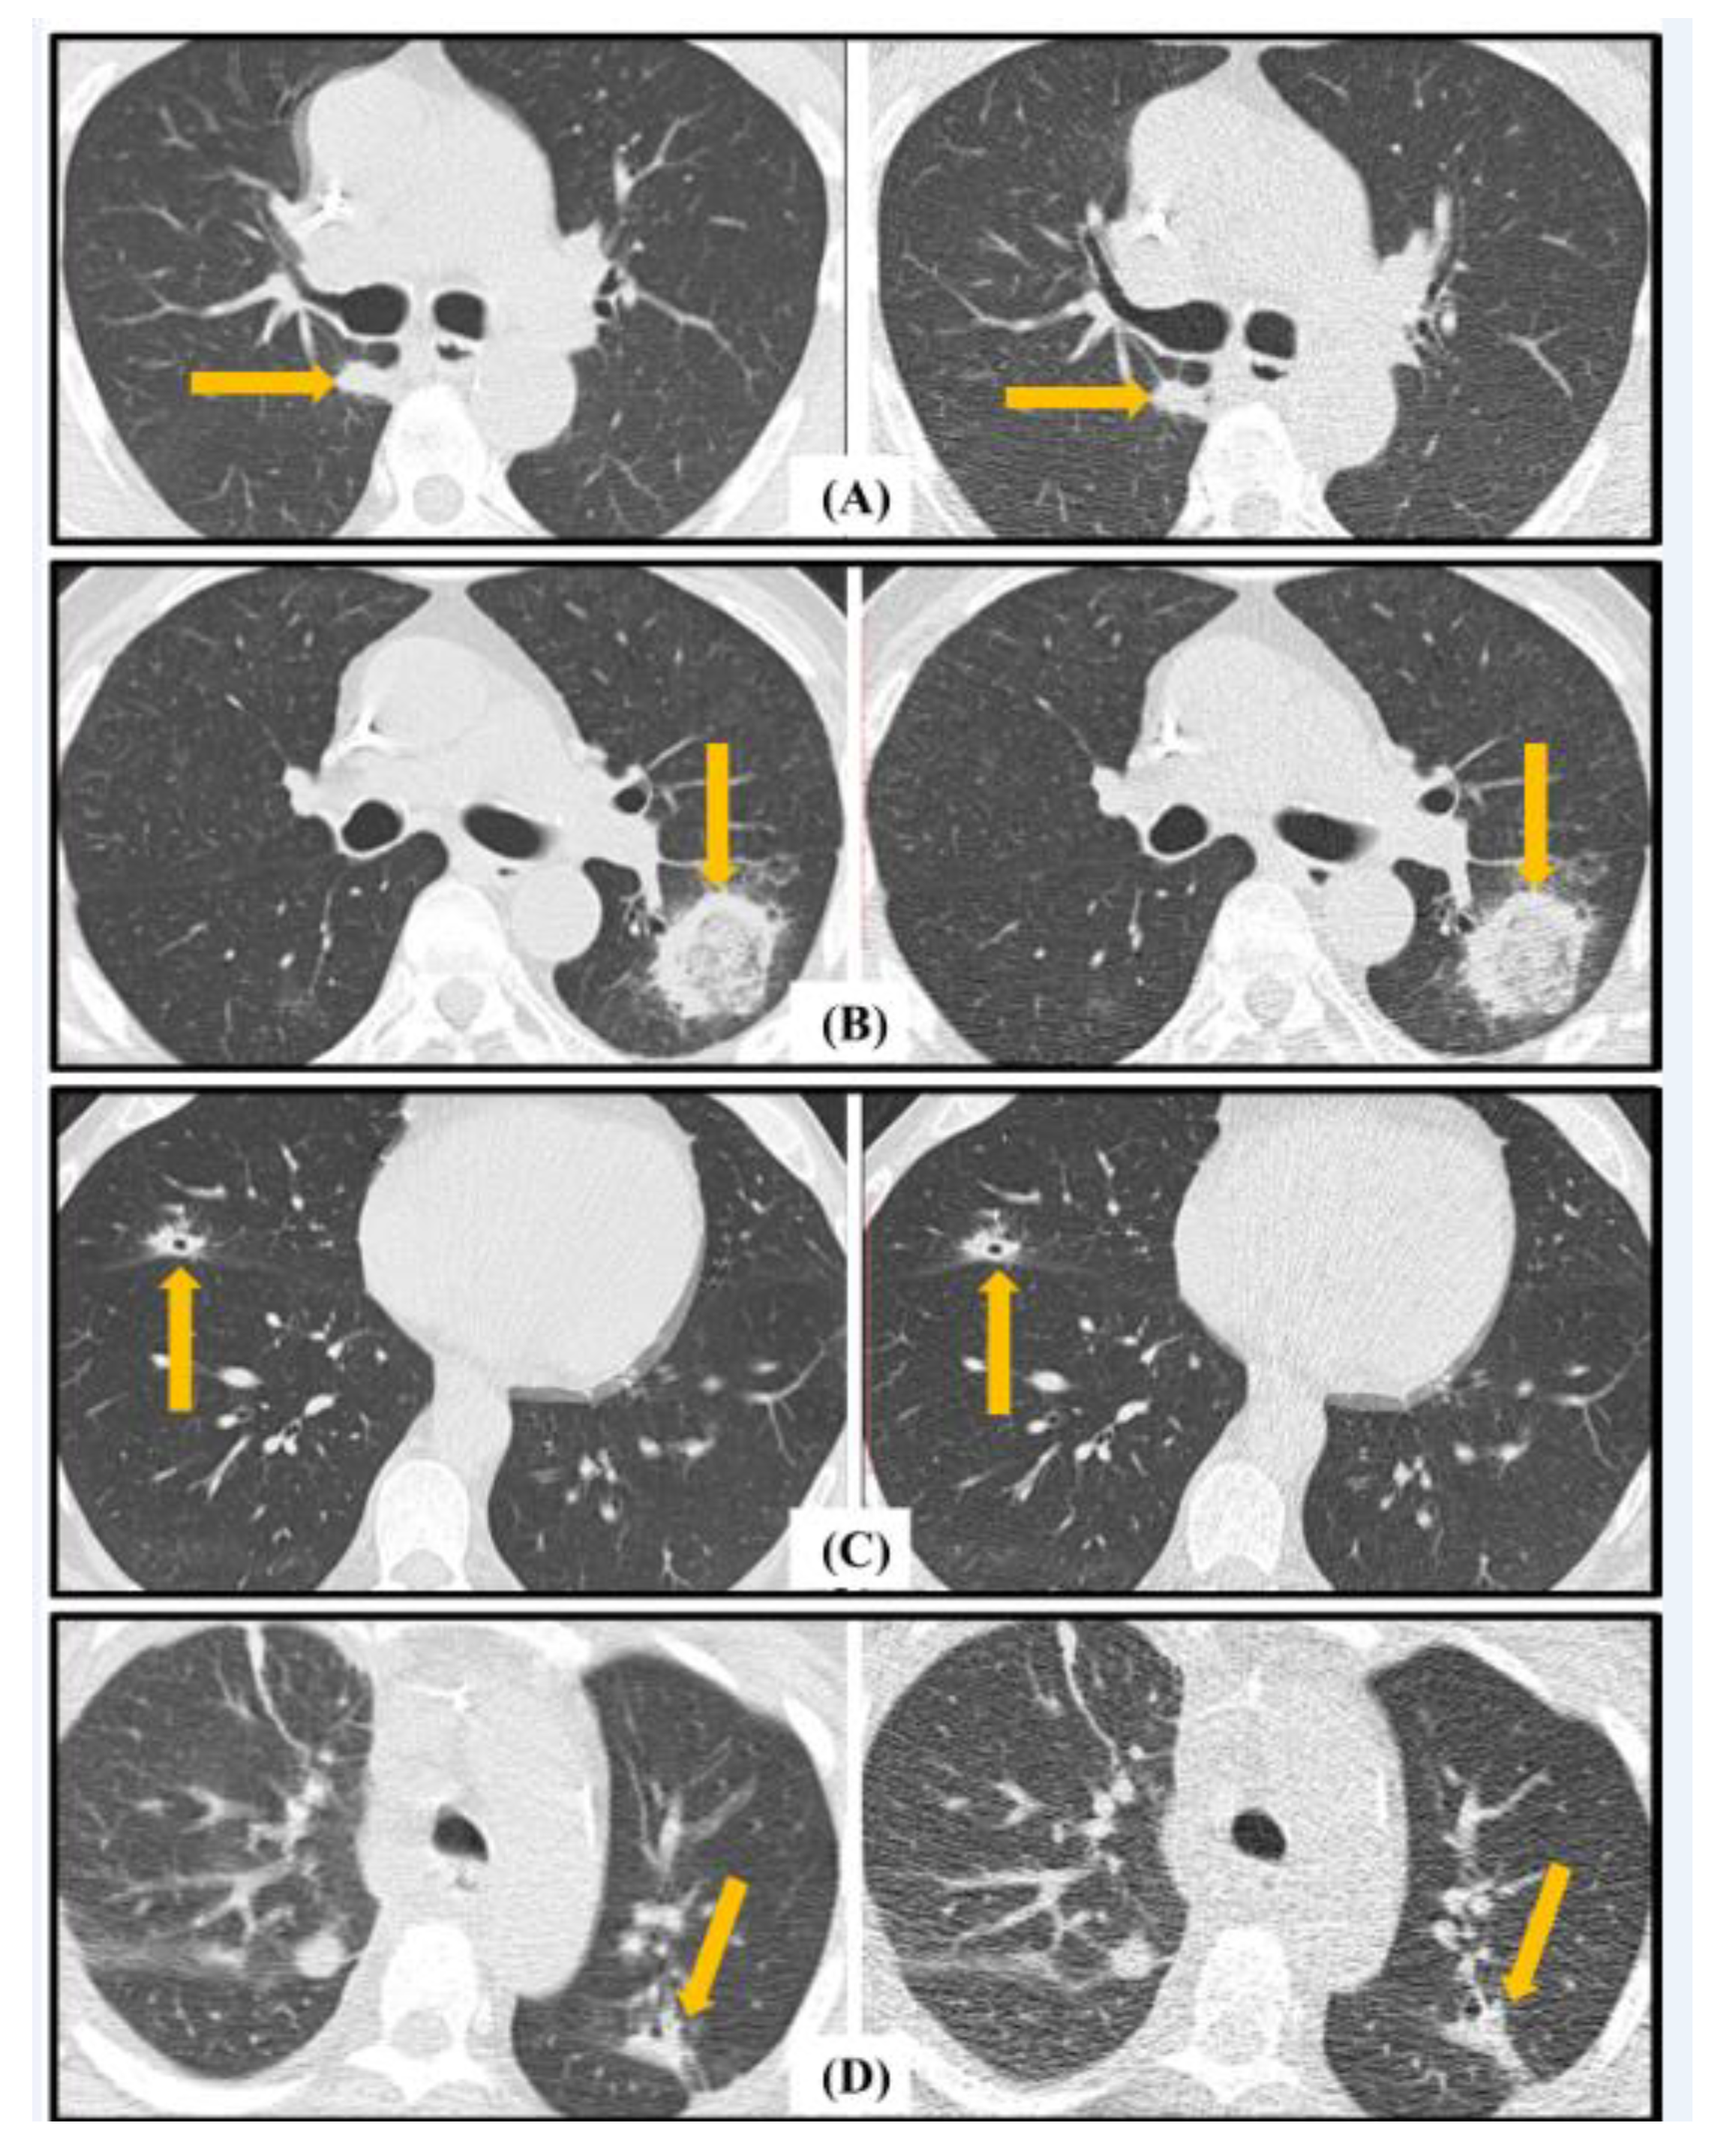

4.3. EORTC Radiological Findings Assessment

5. Discussion